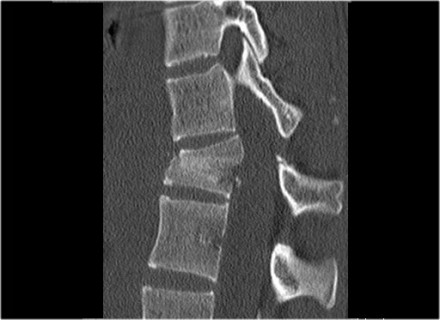

The images are of a patient with a typical bamboo spine as a result of ankylosing spondylitis.

After a fall on his back no fracture was seen on the x-rays.

However the CT shows a thin fracture line through the anterior side of the vertebral body and also through the spinous process.

Continue with the MR-images.

Look at the images.

What are the findings?

Then scroll to the next images.

The findings are:

- Vertebral bodies show marrow edema as a result of a fracture.

- Torn flaval ligament (yellow arrow).

- Fractures through the posterior elements (red arrows).

The TLICS-score is high, because there is distraction and injury to the PLC.